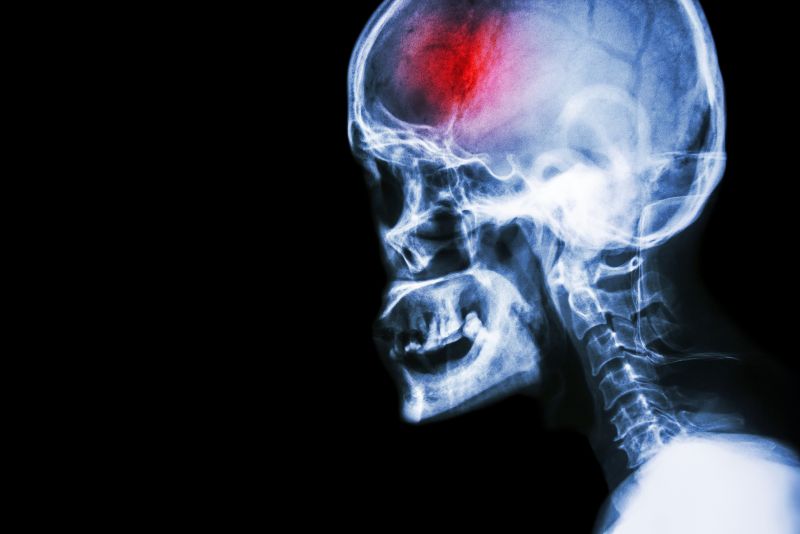

Head X-ray

Head X-rayA stroke is a serious medical emergency that requires immediate action in order to achieve the best eventual outcomes. Early medical intervention, as well as early, consistent and ongoing rehabilitation will positively affect your long term capabilities.  Physical therapy services at FYZICAL Boulder & Horizon can assist you to recover from your stroke and regain your maximum potential.